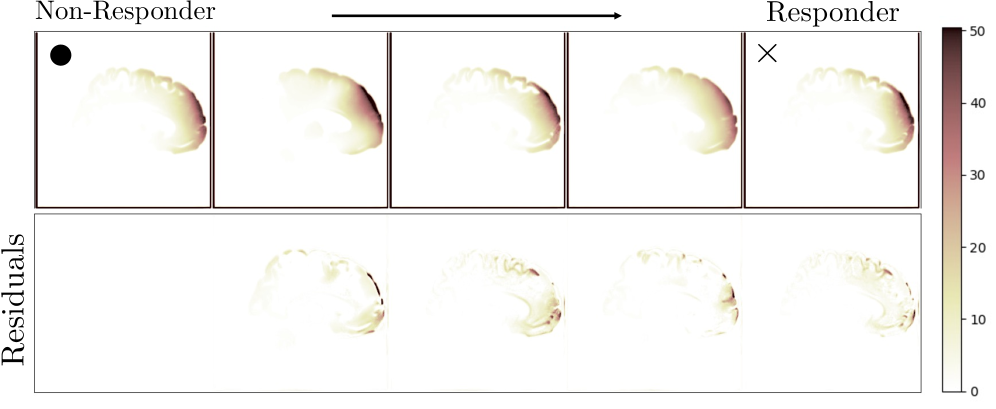

SVM Classification and KDE-Based Class Traversal. We evaluated the ConDA embedding space () on downstream classification by training linear and RBF-kernel SVMs on two tasks: Fluid (steady vs. unsteady laminar flow) and E-Field (treatment responder vs. non-responder). As shown in Tab. 3, classifiers trained on -space consistently outperformed those trained directly in the diffusion latent space across Accuracy, F1, and ROC-AUC, independent of the kernel choice, indicating improved separability of task-relevant structure in . For example, in the E-Field task, an RBF-SVM classifier trained on achieved an F1 score of , a marked improvement over the in . Leveraging the interpretability afforded by the low dimensionality of , we visualized the decision-relevant latent dynamics. We used kernel density estimation to model the class-conditional densities and then interpolated along the vector connecting the peaks of these densities. The resulting sequences, depicted in Fig. 3, illustrate the smooth trajectory of change required for a non-responder E-field pattern to morph toward that of a responder. The color-coded changes reveal specific cortical shifts, providing a tangible and interpretable path toward personalizing targeting strategies.

For classification, we train linear and RBF SVMs with leave-subject-out CV on the TMS E-Field dataset with 110 subjects(responders: change in HAMD-17; non-responders: change in HAMD-17 shown in Fig. 9) and leave-()-out on the fluid dataset (steady: ; unsteady laminar: ) Osafo Nkansah et al. (2024)). Generalization is evaluated on 10 held-out subjects and 8 held-out reporting F1, accuracy, and ROC-AUC. For class transfer, we perform KDE-based interpolation (sklearn.neighbors.KernelDensity) in five steps between non-responder and responder E-fields at a fixed coil angle by locating class-conditional density modes (skimage.feature.peak-local-max) and editing embeddings along the vector connecting mode peaks.